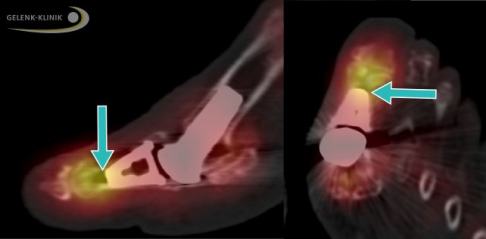

Eine MRT (Magnetresonanztomographie) ist besonders vor gelenkerhaltenden Maßnahmen indiziert, um eine genaue Einschätzung der Situation zu ermöglichen. Die Untersuchung zeigt das Ausmaß und die Verteilung der Knorpelschäden, die Stärke der Knochenreizung und den Befall benachbarter Gelenke. Besonders bei bewegungsverbessernden Maßnahmen scheint das Gelenk zwischen Sesambeinen und Mittelfußkopf eine wichtige Rolle für Restschmerzen zu spielen. Außerdem kommt die MRT zur Planung von Teilprothesen oder elastischem Knorpelersatz (CARTIVA-Implantate) zum Einsatz.

Bei der dynamischen Ganganalyse ist der Druck, den der Fuß beim Abrollen auf den Boden ausübt, relevant. Der Patient läuft über ein Laufband mit Messstation. Das System liefert genaue Daten, in welchen Bereichen der Patient seinen Fuß am meisten belastet. Diese Bereiche sind rot eingefärbt.

Darüber hinaus liefert die Ganganalyse ein ganzheitliches Bild des Bewegungsapparates. So können Fußschmerzen ihren Ursprung auch in einer Fehlstellung der Beinachse oder bei Problemen in der Wirbelsäule haben. Die kombinierte Analyse stellt einen Zusammenhang zwischen Bewegung, Haltung und Schmerz her.